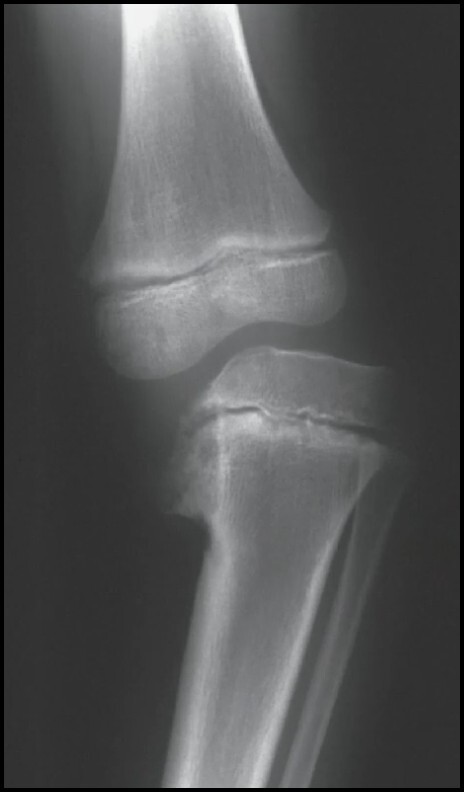

Q

Doença de Blount

Características (4)

A

1. Fise Postero-Medial Irregular

2. Bico Ósseo Metafisário Medial

3. Ponte Óssea Medial

4. Subluxação Tibial Lateral

9

Como mensurar Ângulo de Levine ?

Ângulo formado entre as linhas:

1. Perpendicular ao eixo longo da tíbia

2. Linha entre bico metafisário medial e lateral

10

Predição pelo ângulo de Levine (3) ?

< 11º ( > 95% FISIOLÓGICO)

> 15º ( > 95 % BLOUNT)

11 - 15º : ÁREA CINZENTA